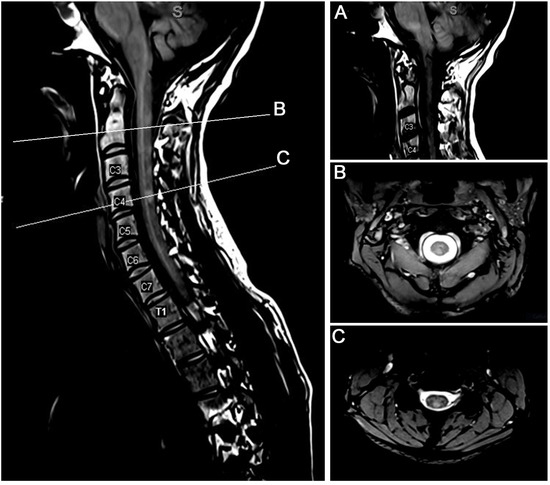

Laparoscopy for relapsing paralytic ileus in multiple sclerosis: a video case report

by Giacomo Chiaro, Corneliu Fratila, Franz Martig, Chiara Zecca and Claudio Gobbi

Swiss Arch. Neurol. Psychiatry Psychother. 2019, 170(2), 1-4; https://doi.org/10.4414/sanp.2019.03012 - 1 Jan 2019

Abstract

Autonomic failure, especially of the gastrointestinal tract, has been detected in a wide range of multiple sclerosis patients with very variable frequencies. Acute manifestations of gastrointestinal dysfunction, however, are rarely reported. We describe an multiple sclerosis patient with a relapsing form of acute [...] Read more.

Autonomic failure, especially of the gastrointestinal tract, has been detected in a wide range of multiple sclerosis patients with very variable frequencies. Acute manifestations of gastrointestinal dysfunction, however, are rarely reported. We describe an multiple sclerosis patient with a relapsing form of acute paralytic ileus in the context of acute autonomic failure requiring surgery. Full article